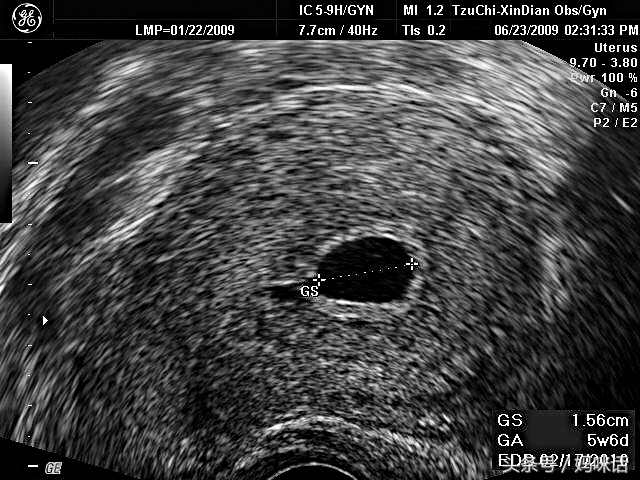

一张照片,应该就是大家的第一次亲密接触。中间那个小黑点,就是位在子宫内的胚囊(gestational sac, GS),胚囊就是胎儿的「房间」。右下角1.56公分就是胚囊的直径,GA(gestation age)是周数的意思,1.56公分直径的胚囊,大约是妊娠5w6d(5周又6天),用胚囊的大小推算,EDD(estimated due date, 预产期)是02/17/2010,大家看懂了吗?